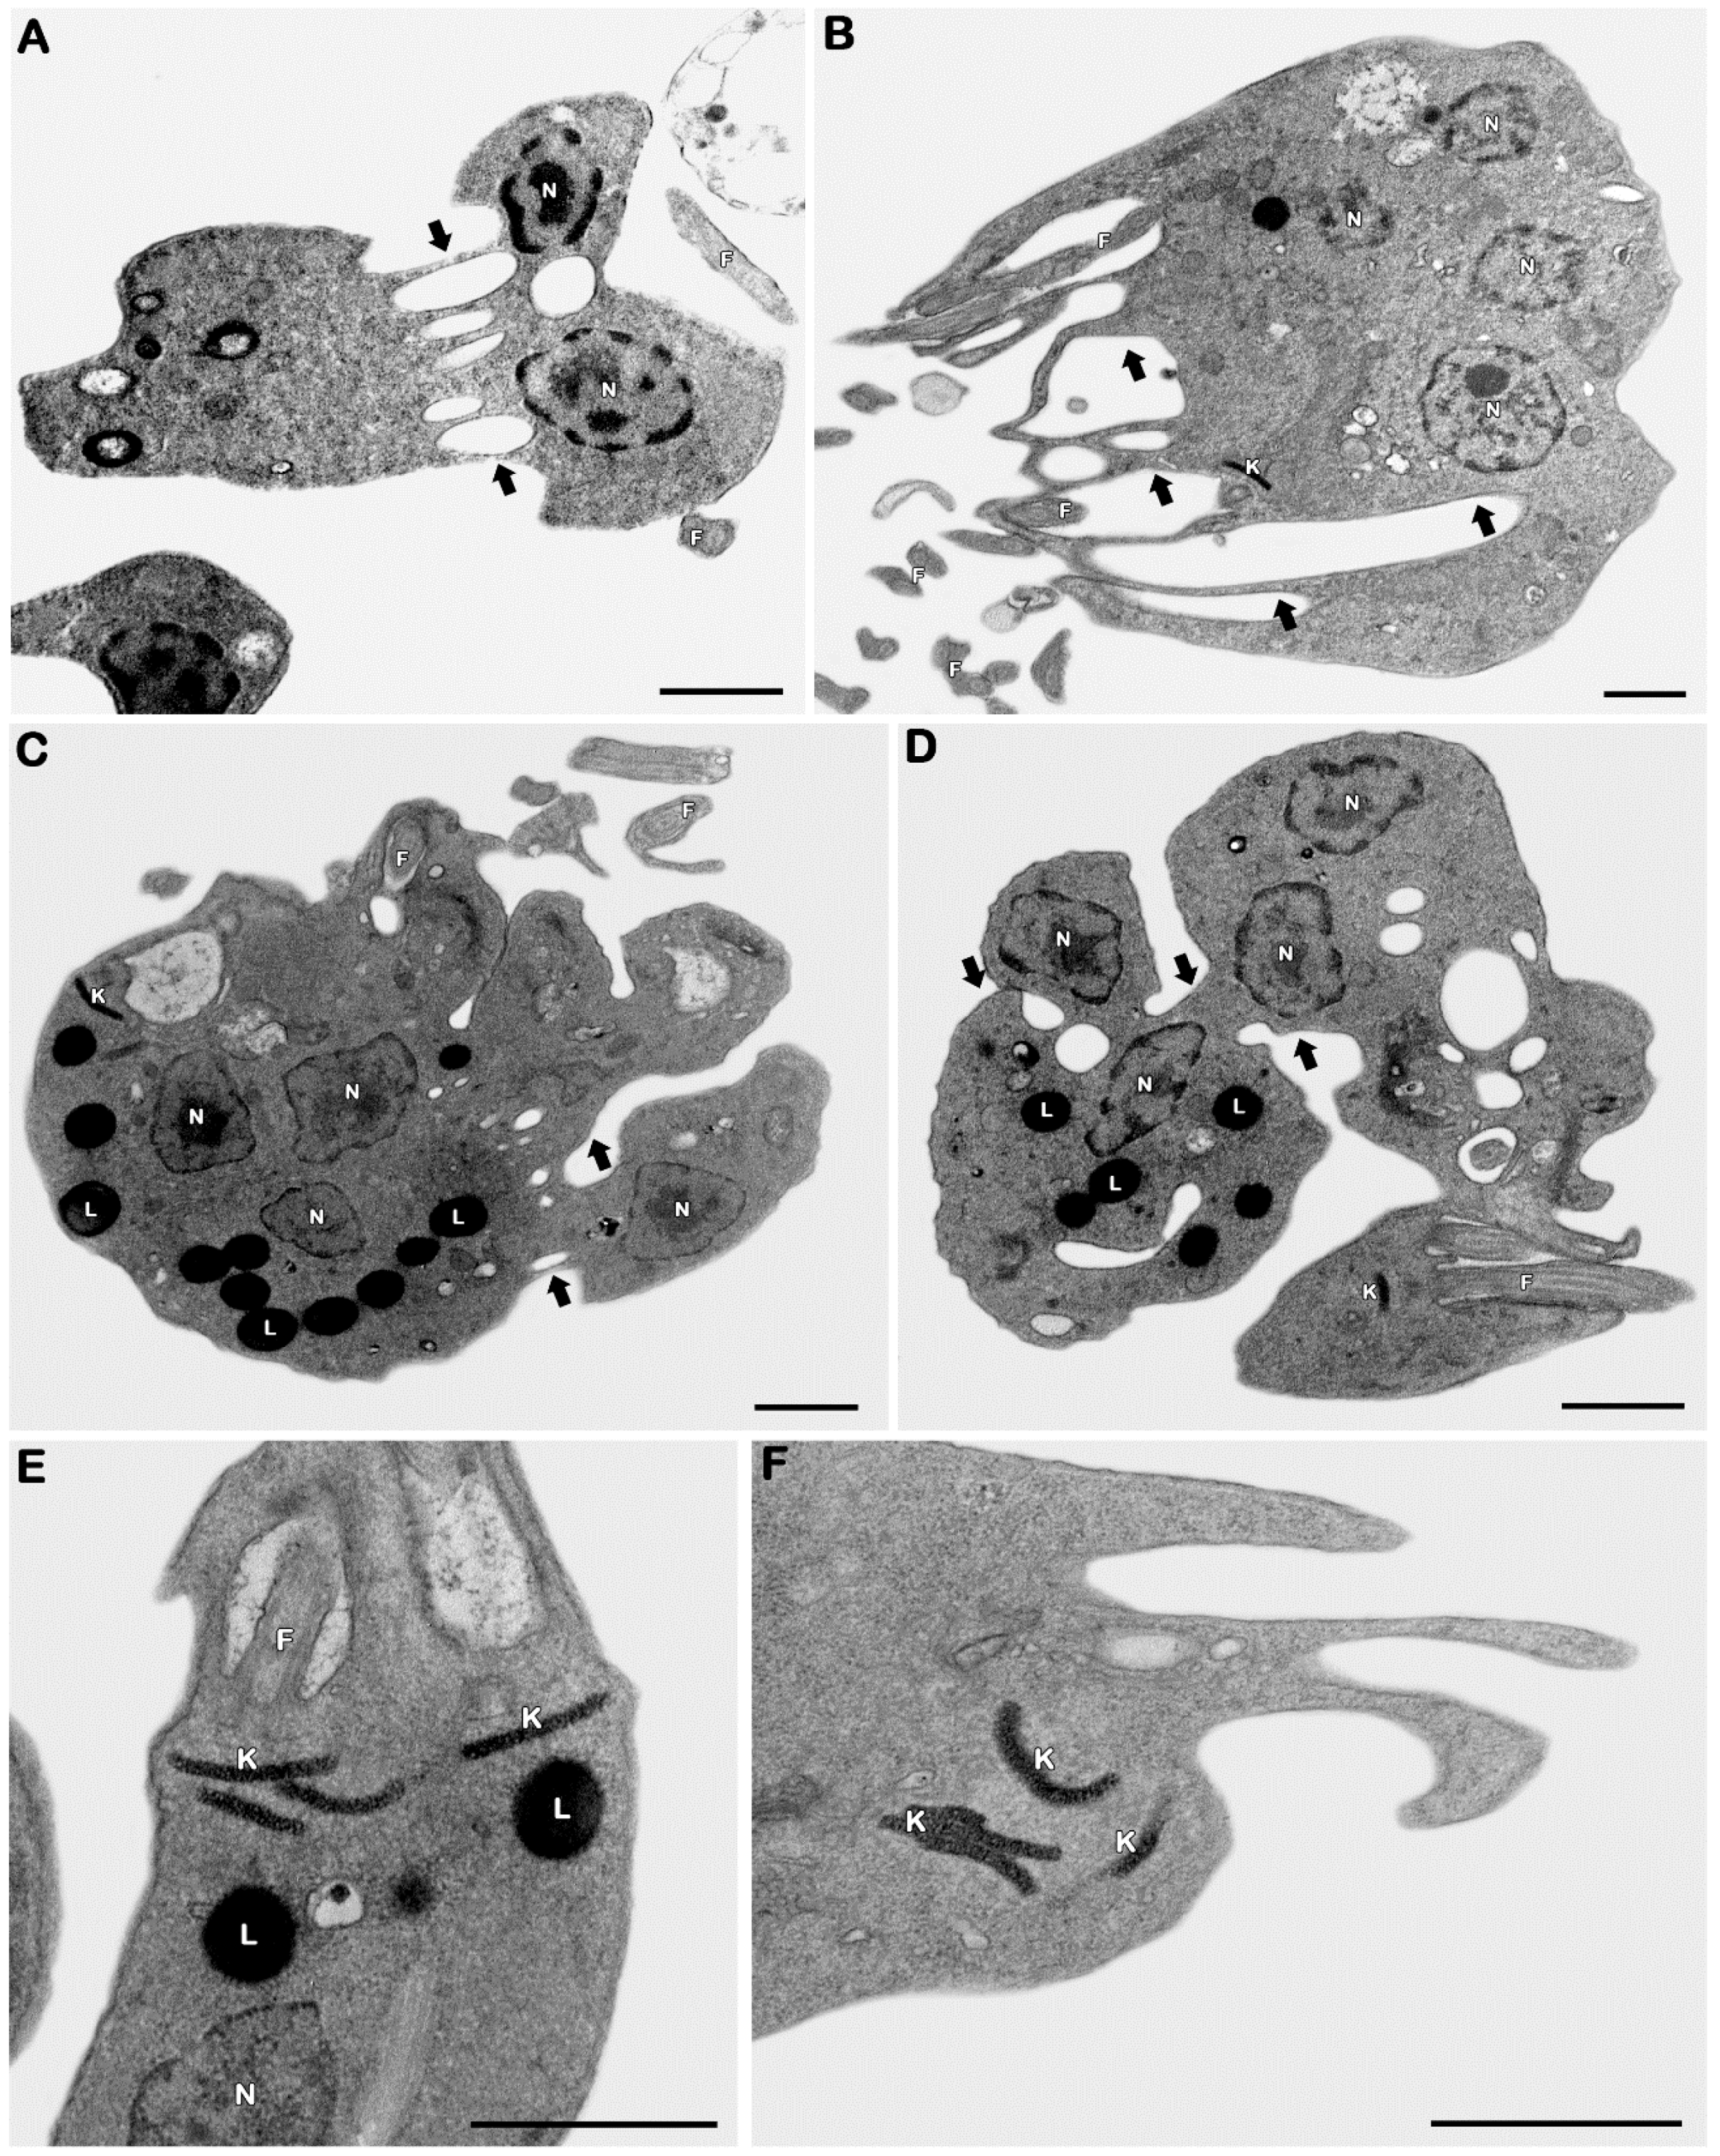

3.2.3. Ultrastructural Analysis

- Borges, V.M.; Lopes, U.G.; De Souza, W.; Vannier-Santos, M.A. Cell Structure and Cytokinesis Alterations in Multidrug-Resistant Leishmania (Leishmania) Amazonensis. Parasitol. Res. 2005, 95, 90–96. [Google Scholar] [CrossRef] [PubMed]

- Grellier, P.; Sinou, V.; Garreau-De Loubresse, N.; Bylèn, E.; Boulard, Y.; Schrével, J. Selective and Reversible Effects of Vinca Alkaloids on Trypanosoma Cruzi Epimastigote Forms: Blockage of Cytokinesis without Inhibition of the Organelle Duplication. Cell Motil. Cytoskeleton 1999, 42, 36–47. [Google Scholar] [CrossRef]

- Moulay, L.; Robert-Gero, M.; Brown, S.; Gendron, M.C.; Tournier, F. Sinefungin and Taxol Effects on Cell Cycle and Cytoskeleton of Leishmania Donovani Promastigotes. Exp. Cell Res. 1996, 226, 283–291. [Google Scholar] [CrossRef]

- Ploubidou, A.; Robinson, D.R.; Docherty, R.C.; Ogbadoyi, E.O.; Gull, K. Evidence for Novel Cell Cycle Checkpoints in Trypanosomes: Kinetoplast Segregation and Cytokinesis in the Absence of Mitosis. J. Cell Sci. 1999, 112, 4641–4650. [Google Scholar] [CrossRef]

- Stefanello, T.F.; Panice, M.R.; Ueda-Nakamura, T.; Sarragiotto, M.H.; Auzély-Velty, R.; Nakamura, C.V. N-Butyl-[1-(4-Methoxy)Phenyl-9H-β-Carboline]-3-Carboxamide Prevents Cytokinesis in Leishmania Amazonensis. Antimicrob. Agents Chemother. 2014, 58, 7112–7120. [Google Scholar] [CrossRef]

- Ambit, A.; Woods, K.L.; Cull, B.; Coombs, G.H.; Mottram, J.C. Morphological Events during the Cell Cycle of Leishmania Major. Eukaryot. Cell 2011, 10, 1429–1438. [Google Scholar] [CrossRef]

- Havens, C.G.; Bryant, N.; Asher, L.; Lamoreaux, L.; Perfetto, S.; Brendle, J.J.; Werbovetz, K.A. Cellular Effects of Leishmanial Tubulin Inhibitors on L. Donovani. Mol. Biochem. Parasitol. 2000, 110, 223–236. [Google Scholar] [CrossRef]

- Castro, E.V.; Yoneyama, K.G.; Haapalainen, E.F.; Toledo, M.S.; Takahashi, H.K.; Straus, A.H. Myriocin, a Serine Palmitoyltransferase Inhibitor, Blocks Cytokinesis in Leishmania (Viannia) Braziliensis Promastigotes. J. Eukaryot. Microbiol. 2013, 60, 377–387. [Google Scholar] [CrossRef] [PubMed]

- Godinho, J.L.P.; Georgikopoulou, K.; Calogeropoulou, T.; de Souza, W.; Rodrigues, J.C.F. A Novel Alkyl Phosphocholine-Dinitroaniline Hybrid Molecule Exhibits Biological Activity in Vitro against Leishmania Amazonensis. Exp. Parasitol. 2013, 135, 153–165. [Google Scholar] [CrossRef] [PubMed]